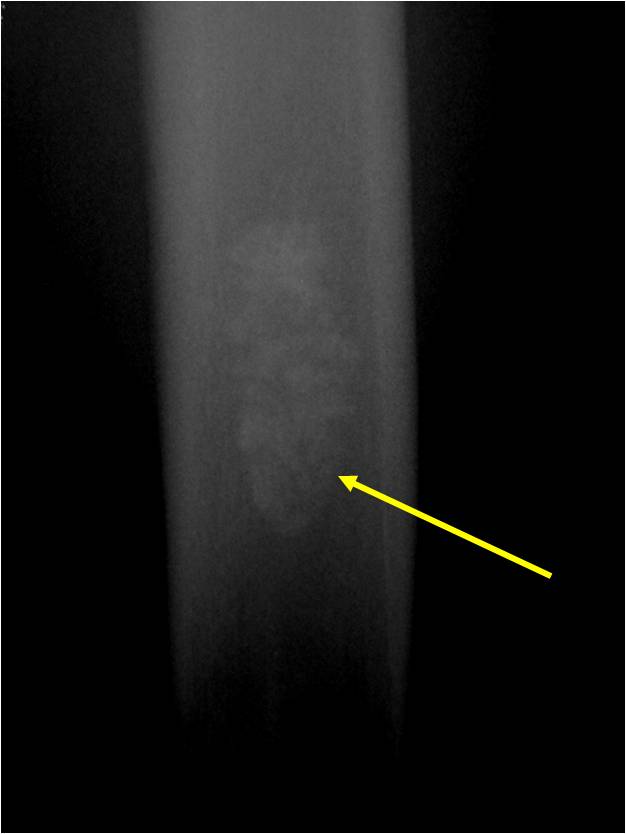

- Localized, radiolucent defect usually with punctate calcifications

Plain X-Ray:

- Geographic lytic lesion

- Central often metaphyseal in long bones

- Can be eccentric also

- Expansile remodeling with thinned cortex

- Chondroid matrix with calcifications in majority of tumors

- Approximately 20% have limited or no calcifications